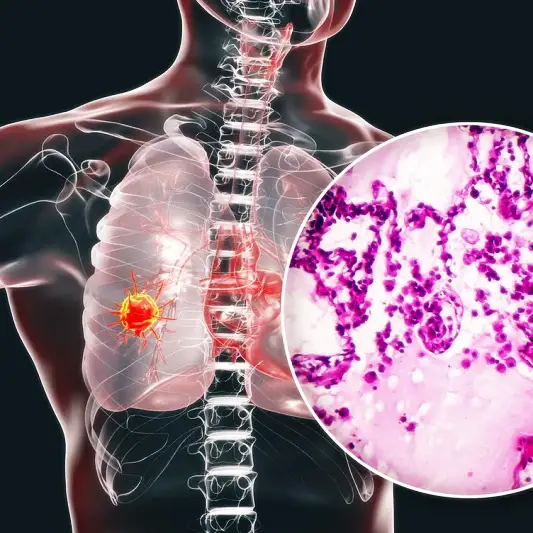

암은 많은 사람들에게 공포를 주는 질병 중 하나입니다. 특히 폐암은 그 중에서도 치명적인 위험이 있는 암 종류입니다. 그러나 폐암이 초기 단계에서 진단되면 생존율이 크게 개선될 수 있습니다. 1기 폐암 진단과 초기 치료 방법에 대해 알아보겠습니다. 폐암 1기 진단은 환자의 증상과 조직 검사, 영상 검사를 통해 이루어집니다. 초기 단계에서 병변의 크기와 위치를 확인하고 암세포의 유무를 확인합니다.

폐암은 악성 종양으로서, 조기에 발견되면 치료 가능성이 크게 향상될 수 있습니다. 그렇기 때문에 폐암 1기 진단이 매우 중요합니다. 일반적으로 폐암은 초기에는 증상이 거의 없거나 미미하여 환자가 자신의 건강에 대해 인지하지 못할 때가 많습니다. 그러나 폐암은 조기에 발견되면 대부분 완치 가능한 암입니다. 따라서 이를 위한 철저한 진단이 필요합니다.

폐암 1기 진단을 위해서는 정기적인 검진이 중요합니다. 폐암 검진에는 흉부 X-선, CT 스캔, PET 스캔 등이 사용될 수 있습니다. 이러한 검사를 통해 의사는 폐암의 존재 여부와 정확한 위치를 확인할 수 있습니다. 또한 폐암의 크기, 종류, 세포의 특성 등을 파악하여 적절한 치료 방법을 결정할 수 있습니다.

폐암 1기는 폐조직 내에서 악성 종양이 형성되었음을 의미합니다. 이 단계에서는 종양이 아직 주변 조직으로 번지지 않고 지역적으로 제한되어 있습니다. 따라서 초기 폐암 치료는 주로 수술로 이루어집니다.

폐암 1기 치료의 주요 방법은 수술입니다. 수술은 종양이 있는 부분을 완전히 제거하는 것을 목표로 합니다. 이를 위해 일반적으로 경피적폐생검(CT가이드하에 종양을 수집하여) 후 확진된 환자에게는 말초폐부분절제술(혹은 폐절제술)이 시행됩니다.